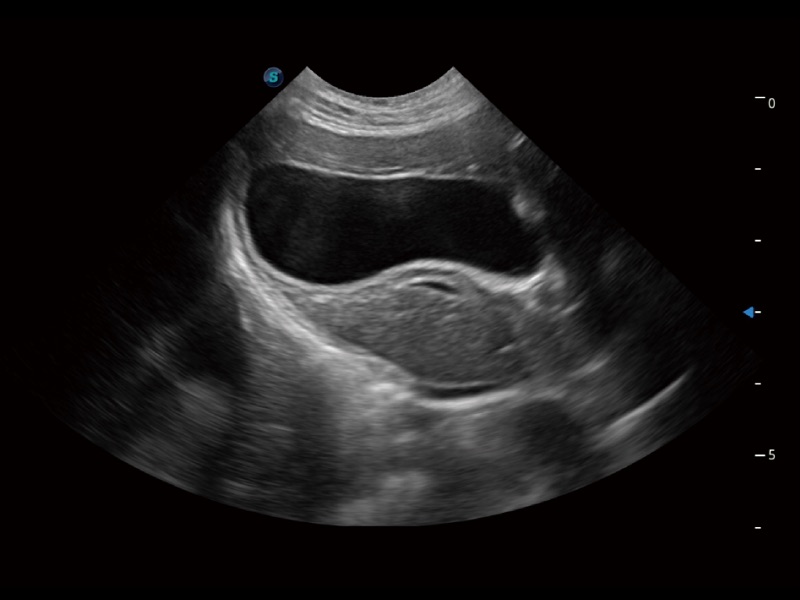

优异的基础图像

(猫)胆囊

(猫)肺动脉血流频谱

(犬)左室长轴血流

(犬)髂动脉血流

(犬)四腔心

(犬)胎儿主动脉弓立体血流

(犬)肝脏

(犬)四腔心MQA